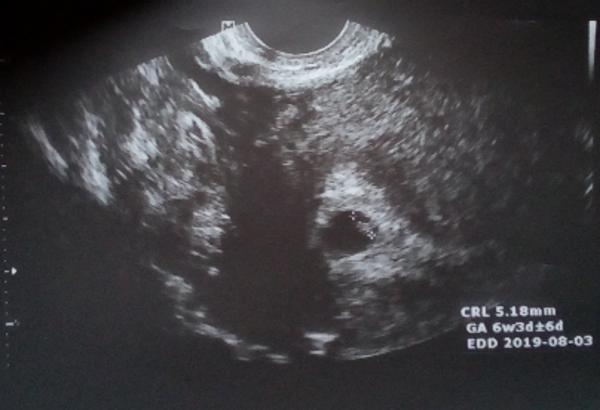

@nikolinka10 ahoj,muj doktor si me objednal az 7 tydnu po zacatku posledni menstruace,ale tim,ze jsem nemela pravidelny cyklus,tak tehotenstvi bylo mladsi(5tt) a byl zatim videt jen zloutkovy vacek.

@nikolinka10 zítra nic neuvidí, leda by ti vzali krev..já jsem šla až když jsem byla 6+1 a stejně mě zval hned za týden znovu, aby to ověřil..ale gratuluju 🙂

@nikolinka10 ten puntík je mimi?

@nikolinka10 ja to teda myslela hlavne tak, ze jeste nebude srdecni akce..neuplne jsem se vyjadrila

@upuska jojo prý je to už mimi no 😊😊